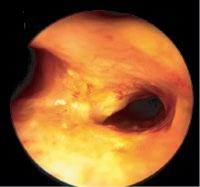

While applying PDT treatment of advanced lung cancer, it was observed that invisible small lesions in the bronchial mucosa became visible due to HPD fluorescence. This proved useful for detection of so-called early lung cancer, that is, in patients with positive sputum cytology with radiologically invisible lesions that could potentially be cured. In further studies, it was shown that by illumination with special light sources, the bronchial mucosa fluoresced without activation by HPD and several systems have been developed in fiberscopes and videoscopes for detection of early cancers by autofluorescence

As autofluorescence was unspecific for diagnosis of malignancy, methods for further analysis were added. Magnifying videobronchoscopes allow more detailed analysis of intra- and subepithelial structure, especially pathological vessels, that are characteristic of development of early bronchial cancer. By selecting smaller spectra in RGB imaging, narrow band imaging (NBI), the visualization of characteristic pathological vessels could be markedly improved. Further increase of resolution toward almost microscopy level could be achieved by EOCT in which an optical scanning beam is reflected from the different layers of the mucosa, providing optical histology images. The most recent technology, confocal microendoscopy, is finally bringing optical resolution to the cellular level [37].

1.10 Early lung cancer. The slight discoloration on white light becomes very prominent by autofluorescence (a). By magnifying endoscopy, the pathological vascularization becomes visible (b), which is even more prominent under NBI (c). In the EBUS image, the superficial lesion ventrally is thickened (3 mm) compared to the normal wall on the left (1.4 mm), but well within the confines of the bronchiall wall and can be treated by bronchoscopic intervention (d).